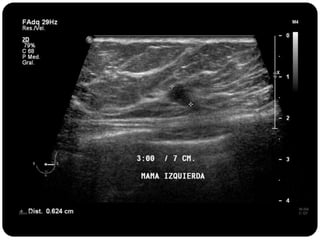

Paciente femenina de 66 años con historia clínica de 1er gesta antes de los 30 años y antecedentes de lactancia positiva, presenta una lesión palpable en la mama derecha. Los estudios radiológicos indican un diagnóstico de bi-rads 5, con biopsias revelando adenocarcinoma lobulillar infiltrante en la glándula mamaria derecha y adenocarcinoma ductal in situ en la izquierda. El caso fue evaluado por las doctoras Jacqueline Preciado Vargas y Beatriz E. González Ulloa.